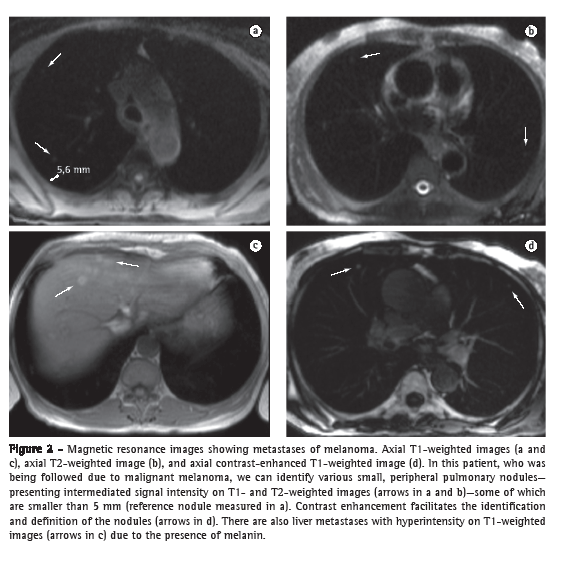

The accuracy of MRI in detecting nodules larger than 4-5 mm is greater than is that of routine X-ray, and the specificity and sensitivity of MRI can be as high as 93% when compared with those of multidetector CT.(18) The sensitivity of MRI is directly related to the size of the nodule. Sensitivity is lower for nodules smaller than 5 mm, whereas it is nearly 100% for the detection of nodules ≥ 10 mm (Figure 2). Therefore, MRI of the lung (principally with the HASTE and 3D GE sequences) should be used as a complementary test in studies of the heart and chest wall, as well as in those of mediastinal lesions. It can also be used as an alternative to CT in screening for lung metastases. The principal limitations of MRI in the study of focal pulmonary lesions include its limited ability to characterize calcified lesions and to detect lymphangitic carcinomatosis.(18-20)